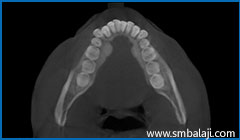

3D Cone Beam CT (CBCT) image showing impacted lower right wisdom tooth, affected second molar and large cyst lesion in right lower jaw